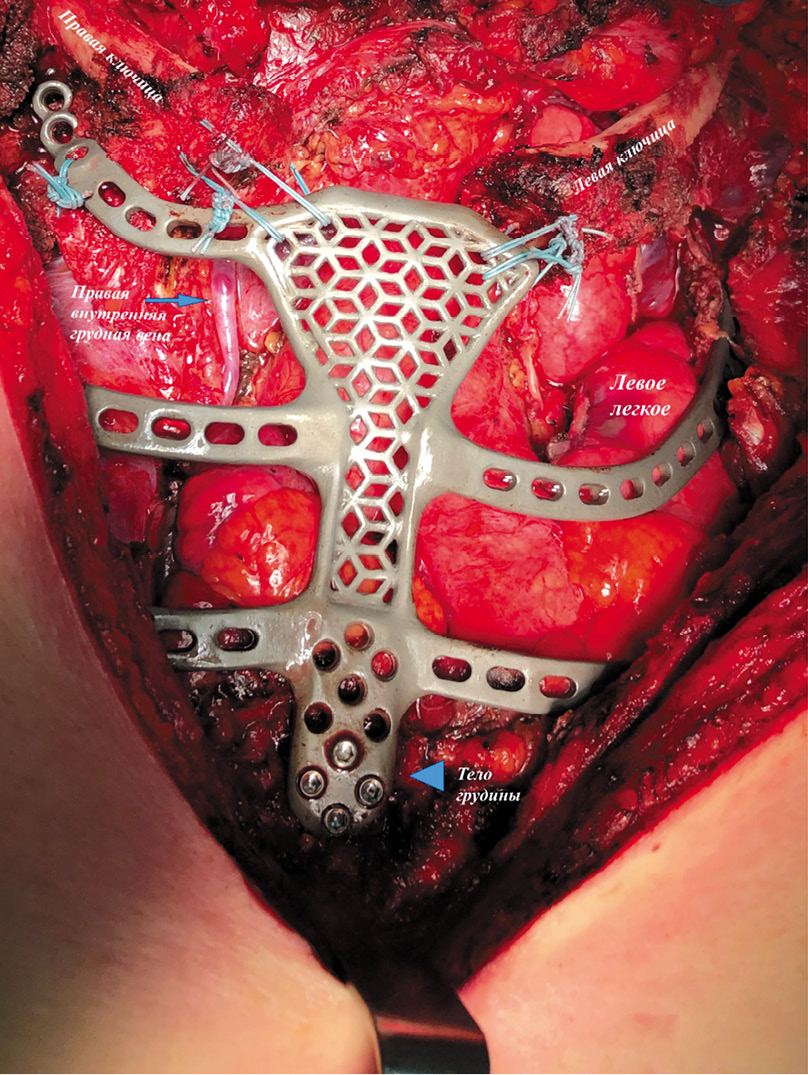

При позитронно-эмиссионной томографии/компьютерной томографии в верхнем средостении определялось многоузловое кистозно-солидное объемное образование с бугристыми контурами, прорастающее в рукоятку и тело грудины, I ребро слева, аксиальными размерами (общие размеры вместе с мягкотканным компонентом рукоятки грудины) 90×42×70 мм, с инвазией в левую плечеголовную вену и формированием опухолевого тромба до уровня верхней полой вены. Опухоль оттесняет прилежащую легочную ткань и интимно прилежит к сосудистым структурам средостения. Накопление 18F-фтордезоксиглюкозой в опухолевом конгломерате SUVmax – 27,9 (рис. 1).

Рис. 1. Позитронно-эмиссионная томография органов грудной клетки. / Fig. 1. Positron emission tomography of the chest.